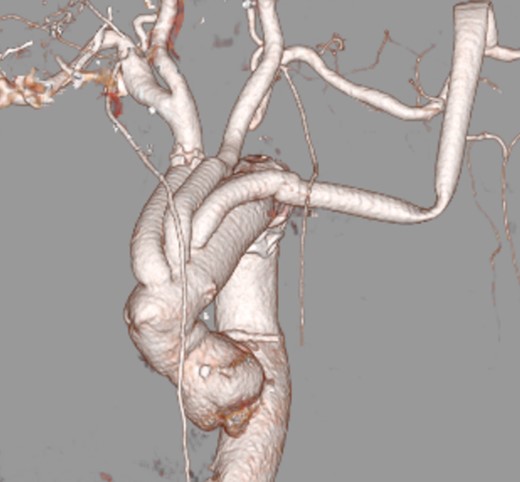

After admission, carotid ultrasonography revealed a large, soft plaque with ulceration in the IA and a very mobile soft plaque in the LSA (Fig. 3). EVT was thus considered too dangerous, and TAR using a four-branched prosthesis was planned. Intraoperatively, bilateral axillary arteries were initially exposed, and an 8-mm vessel prosthesis was anastomosed. Median sternotomy was then performed. Cardiopulmonary bypass was established with arterial perfusion via bilateral axillary arteries and bicaval venous drainage. TAR was performed under hypothermic circulatory arrest with antegrade selective cerebral perfusion, then the brachiocephalic artery and LSA were clamped and the left common carotid artery (LCA) was intubated. To avoid hoarseness due to injury of the left recurrent laryngeal nerve, a hybrid prosthesis (FROZENIX, Japan Lifeline, Tokyo, Japan) was used and a distal anastomosis was created between the LCA and LSA. The LCA was ligated and the prosthesis, which was anastomosed to the left axillary artery, was brought into the mediastinum and anastomosed with a branch of the four-branched prosthesis (Fig. 4). The postoperative course was uneventful and the patient was discharged on postoperative day 16 (Fig. 5).

A soft plaque with ulceration in the IA (A, B) and a very mobile soft plaque in the LSA (C, D).